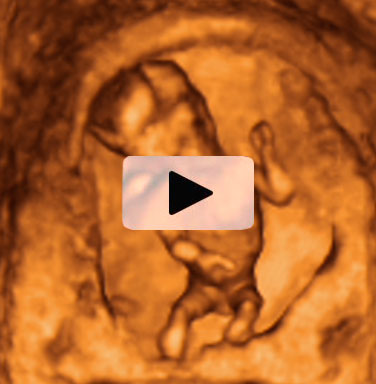

Se pueden identificar los genitales masculinos

Es impactante ver los movimientos de este bebé de 13 semanas de gestación, que parece bailar en un escenario. En la ecografía 4D se aprecian perfectamente todas sus estructuras básicas (cabeza, tronco, extremidades...), incluso los genitales masculinos. Destaca la bipedestación de la figura -se encuentra erguida-, que parece más humana de lo que podríamos imaginar a esa edad gestacional.

Tras ver esta ecografía, cuesta creer que este bebé tenga tan sólo 13 semanas de gestación. El bebé tiene unos movimientos muy humanizados a pesar de su corta edad gestacional.